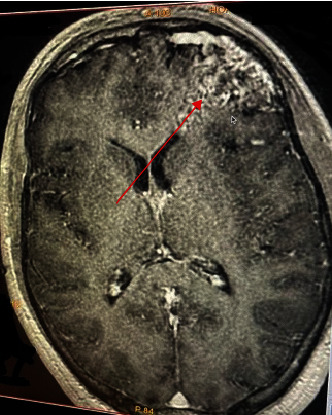

Background: In psychiatry, anatomical abnormalities are sometimes forgotten, and this can mislead doctors into thinking that the diagnosis is purely psychiatric. A physical examination is important whenever it is possible. Even though cerebral arteriovenous malformations (cAVMs) are rare and can go unnoticed, in some cases they can cause clinical symptoms, which is a complication. Case Presentation. In this case, we describe a patient with no prior medical or psychiatric history having a cAVM diagnosed after showing psychotic symptoms (delusion and disorganized thoughts and behavior). The deep 4 × 5 cm cAVM was discovered after admitting the patient to psychiatric ward, the neurological cause has been considered after a recorded seizure, which brings the following question: Is the clinical presentation a direct result of the cAVM or is it postictal?

Conclusions: An abnormality leading to another, here is how we could describe our patient's psychopathology leading to psychotic symptoms. The two hypotheses explaining this case report have a low rate of occurring making this a rare case. Either way, neurological cause cannot be overlooked even if the clinical presentation is typical.